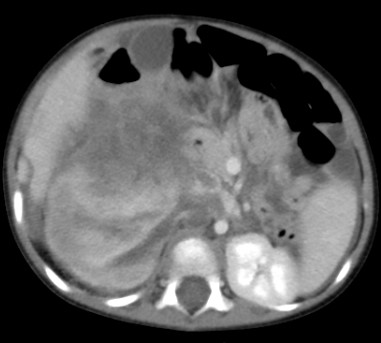

A 21-month-old boy presented with abdominal pain of 2 weeks’ duration which had become more severe over 4-5 hours. An Ultrasound showed a large (9 × 11 cm) mass in the upper pole of the right-side kidney.

An urgent CECT abdomen showed a large 11 × 12 cm Tumour in the upper pole of right kidney (Figure 7). The mass was heterogeneous, contrast enhancing and with areas of necrosis and haemorrhage. The hilar nodes were enlarged and there was a moderate amount of free fluid with several suspicious metastatic lesions in the liver. The impression was of a suspected ruptured Wilms Tumour

Figure 7. CECT suspicious of tumor rupture